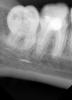

diesel87 Опубликовано 3 февраля, 2013 Поделиться Опубликовано 3 февраля, 2013 Добрый вечер коллеги, такая ситуация: Зуб 47 - дефект пломбы, по краям рецидив кариеса. Перкуссия безболезненна, термопроба отрицательна. Решили хорошо все сделать. Снимок Сразу вопрос: Что думаете по поводу воспалительного процесса на апексах? (мне вот спокойно все кажется) Начал распломбировывать канальцы, дистальный сразу поддался, а медиальные стали противится, как в стекло))), поставил Ларгаль на 3 дня. Через 3 дня: хотел поиграться Эндочаком, как выяснилось прям перед приемом пациента, поменяли наконечник на УЗ и насадка Эндочака теперь не подходит... решил попробовать так, в медиально-щечный 15 К-файл и к нему подношу насадку УЗ и немного шерудю им в канале, потихоньку стал двигаться к заветному сокровищу в виде каналонаполнителя...дошел до него, прям чувствую файлом, взял 10 Н-файл и стал пробовать подцепить его, прям в него вхожу, достаю файл, кончик по наполнителю изогнут))) блин, как на рыбалке, так и хочется подсечь)) вот крайний снимок а так хочется его достать оттуда, не обойти, а именно достать)))перенес удовольствие еще на тройку дней, только уже с Эндосольвом в каналах), завтра буду рыбачить)) Еще вопрос: подскажите как мне его оттуда извлечь, уж больно хочется. Всем спасибо. Ссылка на комментарий

diesel87 Опубликовано 3 февраля, 2013 Автор Поделиться Опубликовано 3 февраля, 2013 А что по поводу апексов думаете? Меня коллега сбила что на медиальных выросло что-то, а я по другому снимок вижу. Нет, не РФ зуб. Ссылка на комментарий

Ico Опубликовано 3 февраля, 2013 Поделиться Опубликовано 3 февраля, 2013 По снимку похоже,что уже рубите не туда.А для чего Вам его доставать?!Пациент уже пережил овер в нижнечелюстном))) Ссылка на комментарий

diesel87 Опубликовано 3 февраля, 2013 Автор Поделиться Опубликовано 3 февраля, 2013 коллега предположила что в м-я что-то наросло, м-щ щель хорошо просматривается и спокойно все, а вот м-я как бы напрягает немного...или уже "жирафа насмотрели"..)) Ссылка на комментарий